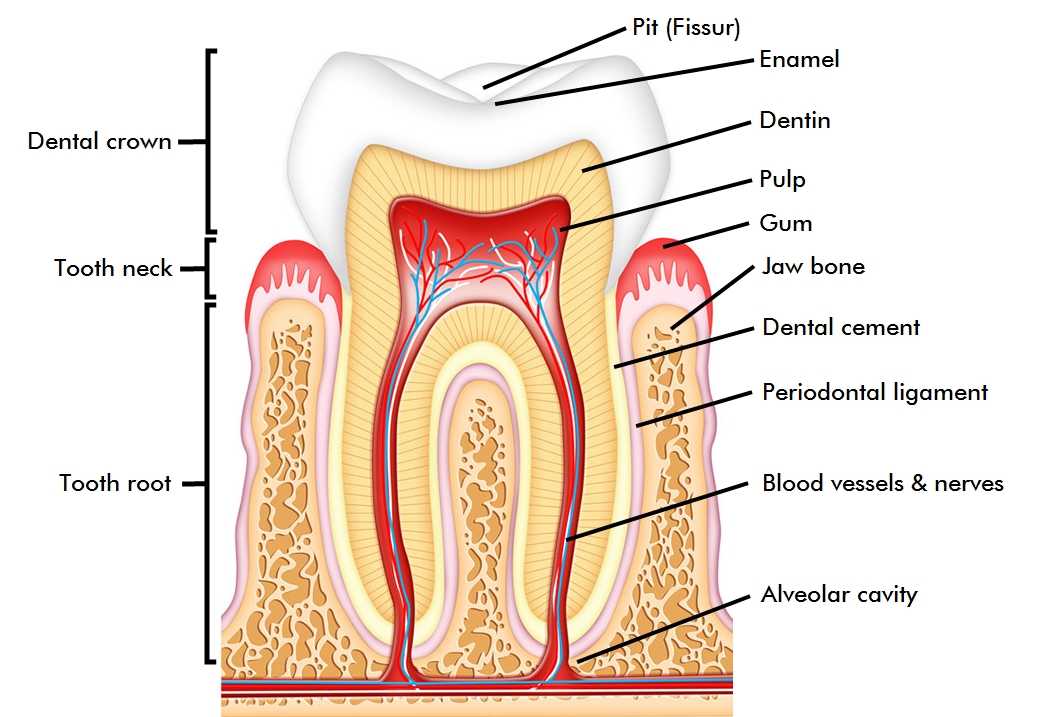

A tooth can be divided into the following parts: